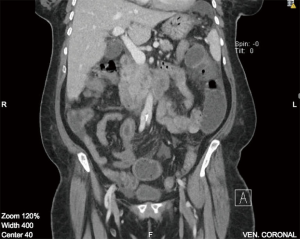

On imaging, plain film abdomen showed dilated small bowel loops and multiple air fluid levels on erect view. Chest X-ray showed no free air under the diaphragm. Computed tomography (CT) of the abdomen and pelvis with IV and oral contrast was done showing prominent dilatation of the jejunal small bowel segments, compatible with obstruction. On the jejunoileal junction and proximal ileal segments there was appearance of intussusception and thickened wall of the ileal segment (6 cm thickness) (Figure 1). Distal ileal and colonic segments were collapsed. There was perihepatic, perisplenic and intrapelvic free fluid. Furthermore, there was a small amount of free air focus in the subhepatic area (Figure 2) with bilateral small pleural effusions. No suspicious lymph nodes were detected.